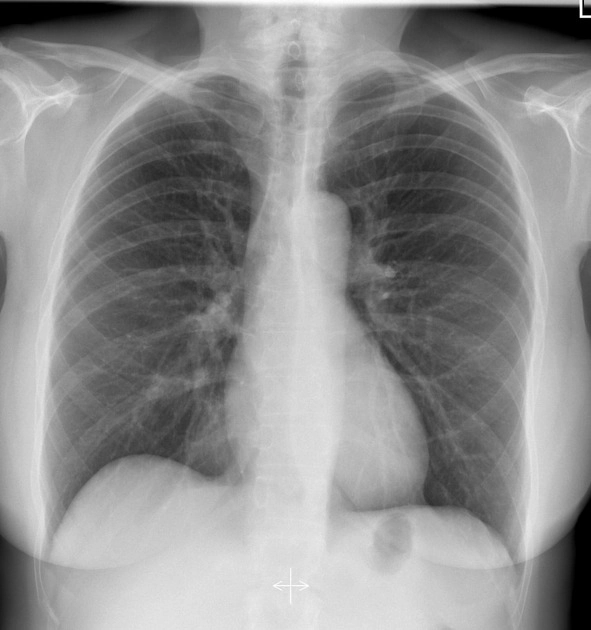

X-quang ngực thẳng bình thường (Chest Radiograph)